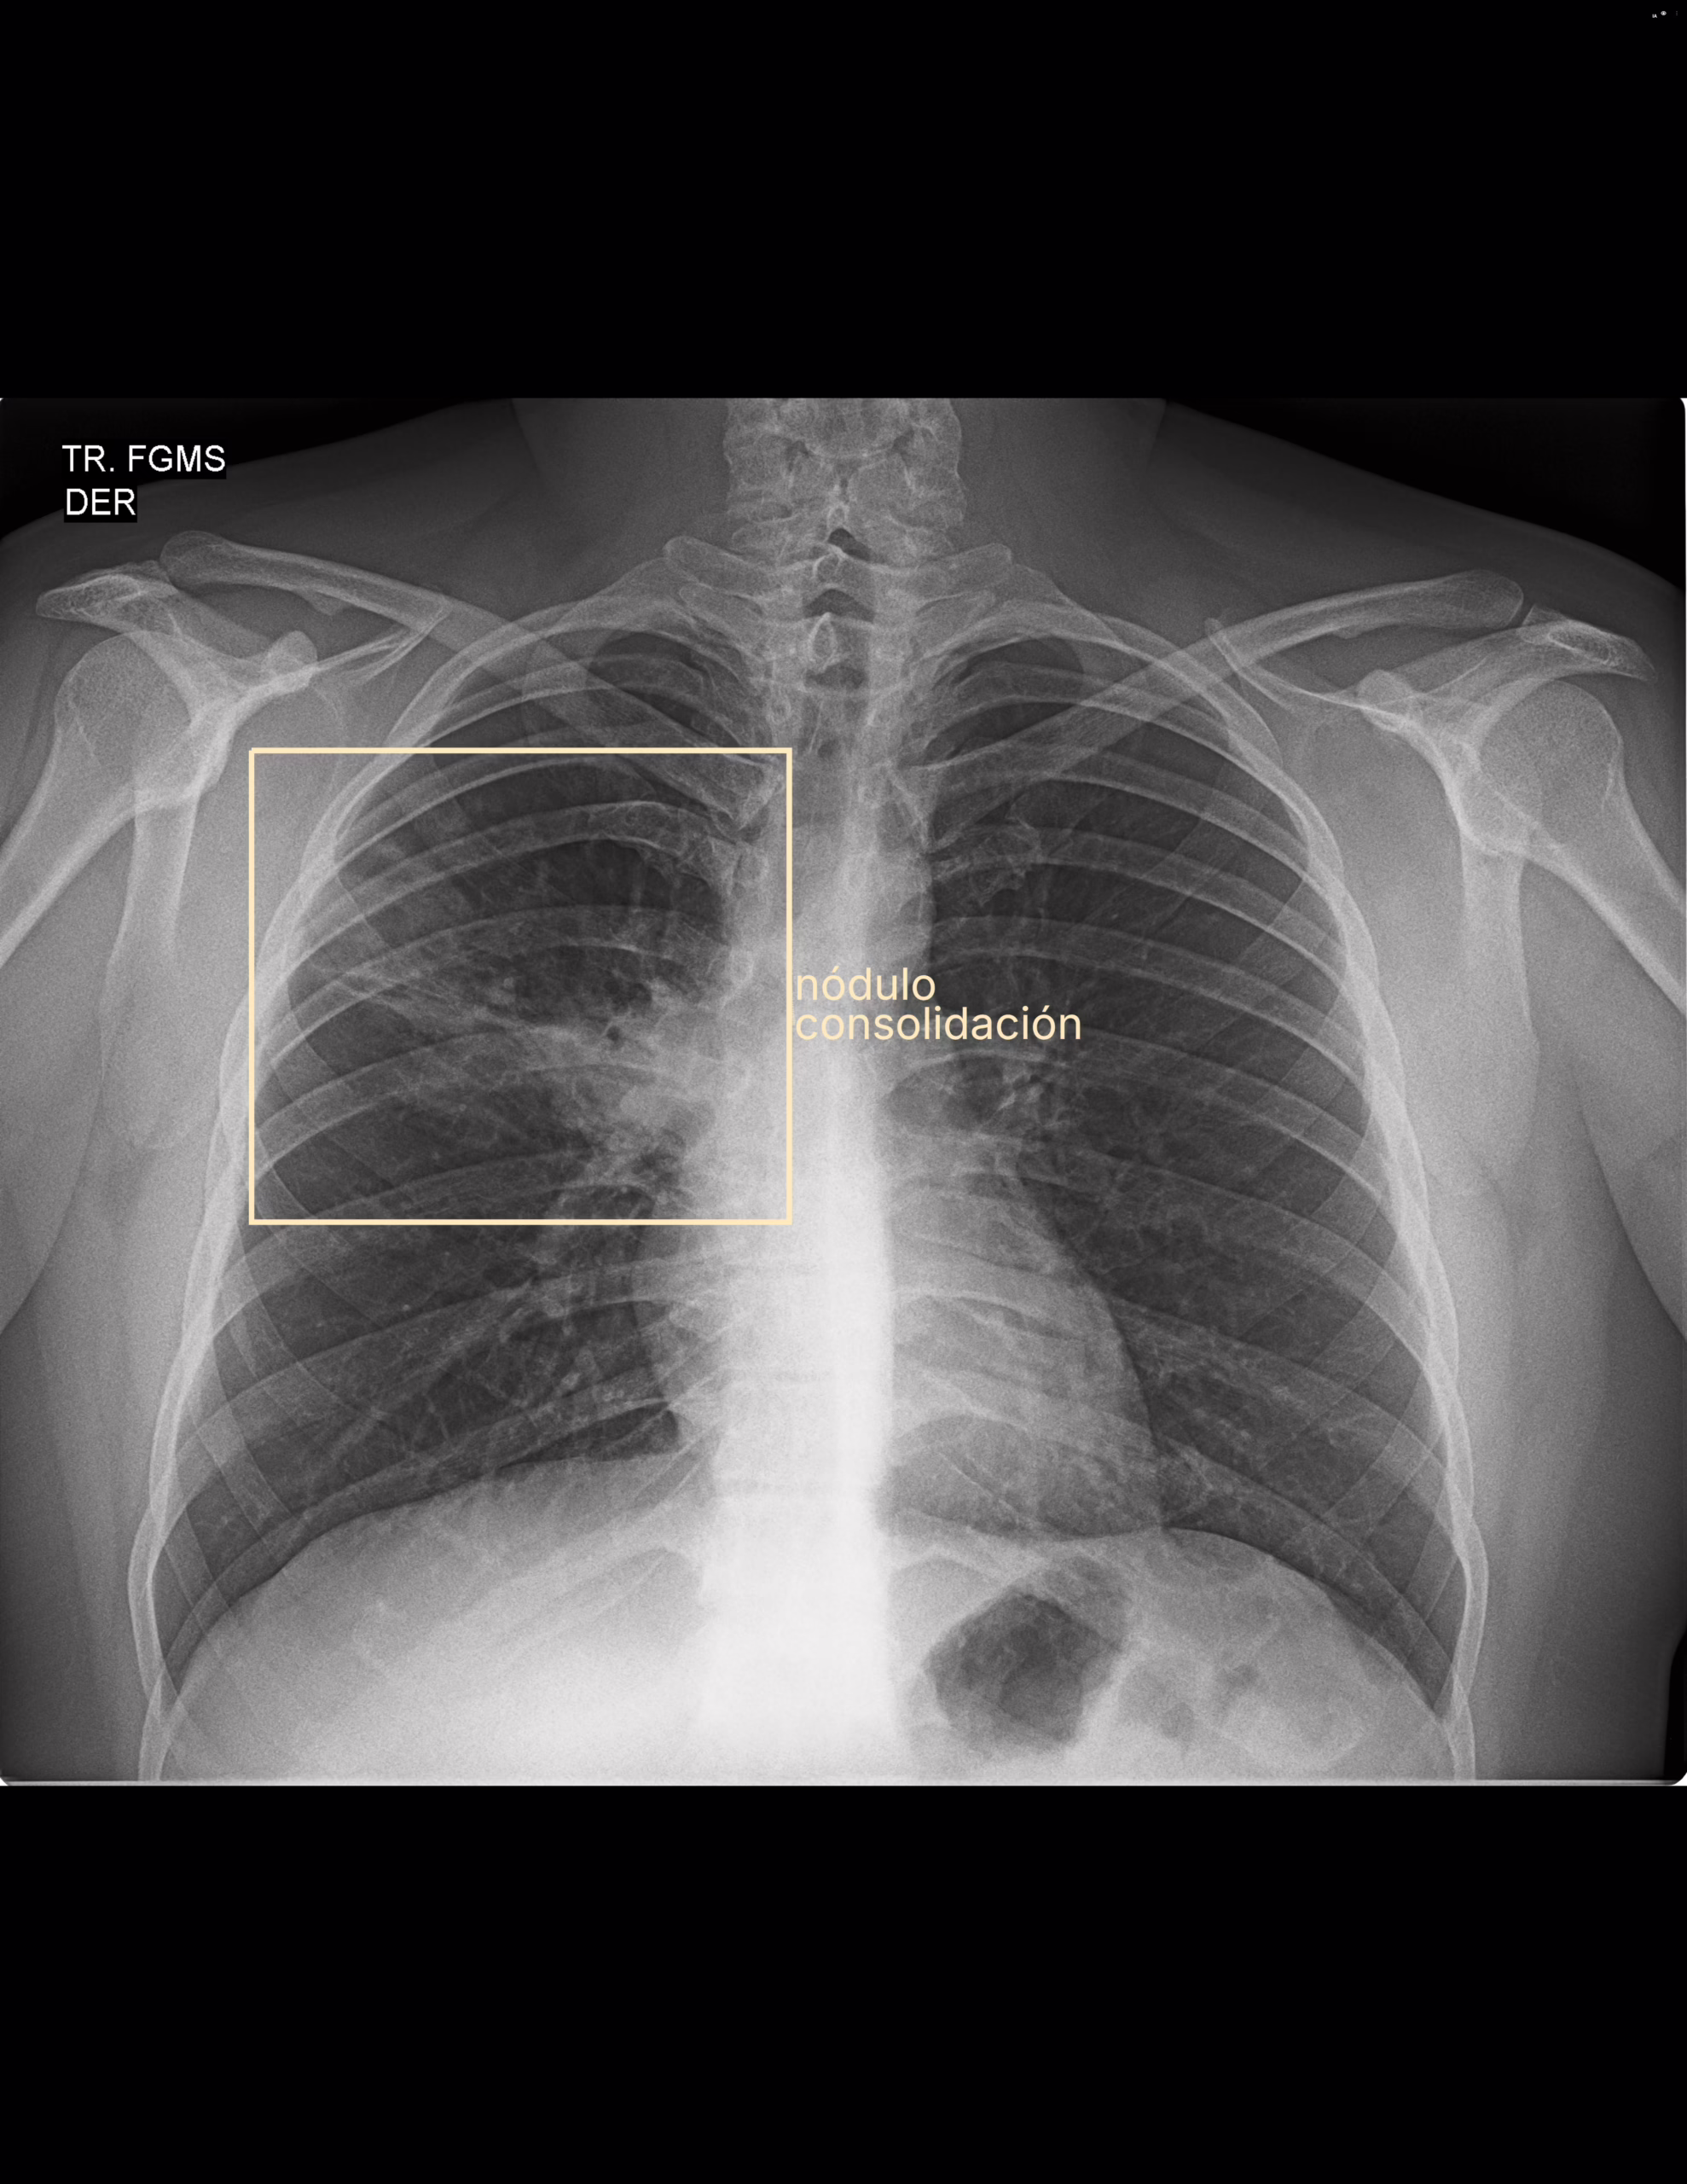

Se interpreta rx tele de tórax observando los siguientes hallazgos:

Parénquima pulmonar heterogéneo con consolidación de lóbulo superior de pulmón derecho

Impresión diagnóstica

Datos de neumonía de lóbulo superior de pulmón derecho